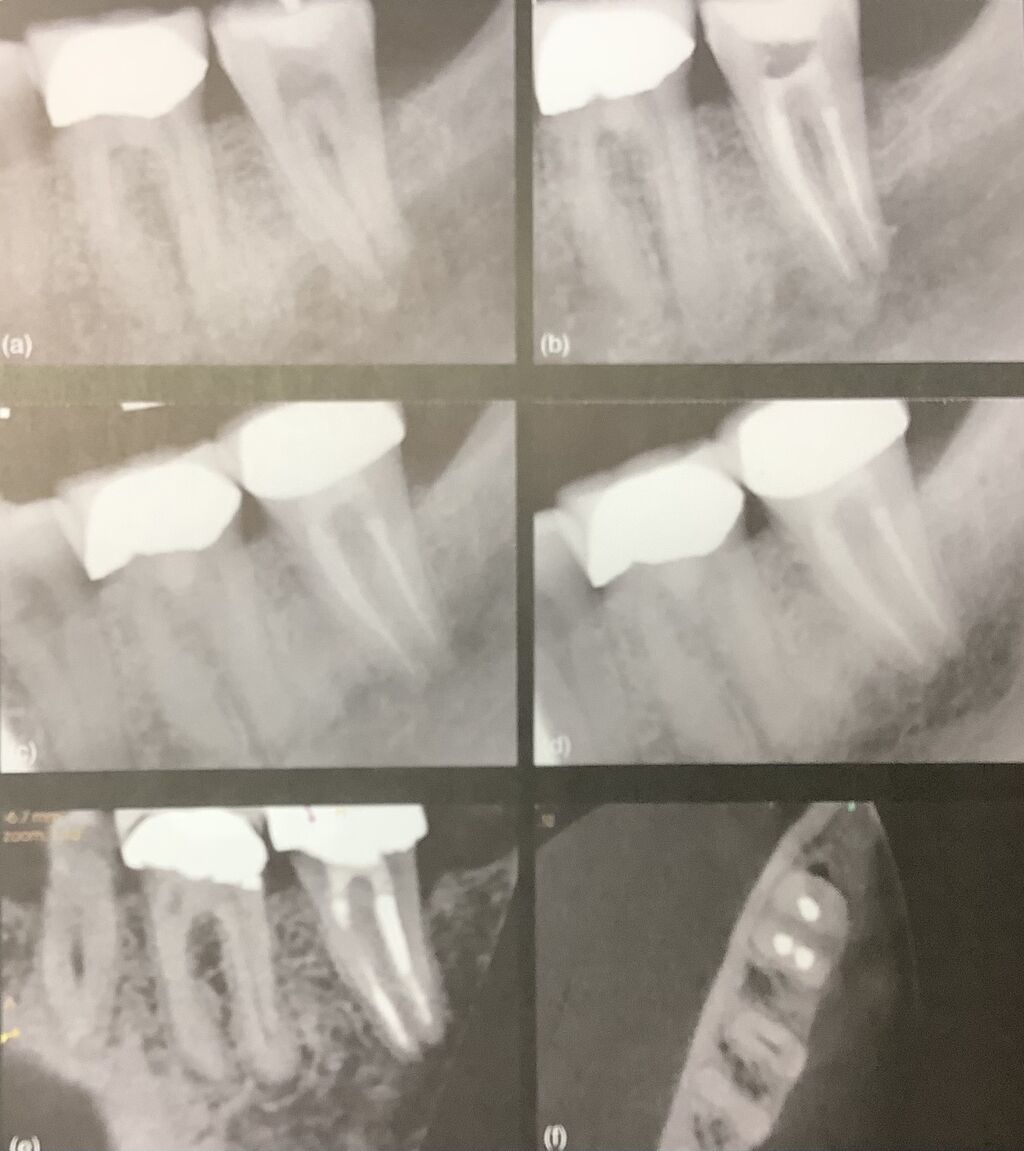

下は8年後にCBCTで確認されたそうです。

流石の治り具合です。